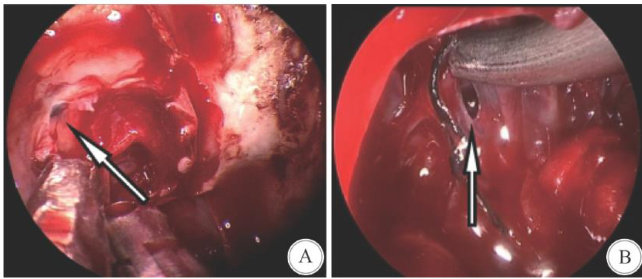

Abstract: Objective To explore the clinical effect of individualized sellar floor reconstruction in different flowrate of cerebrospinal fluid leakage in endoscopicsurgery forpituitary macroadenoma. MethodsThe clinical data of 15O patients who underwent transnasal endoscopic resection of pituitary macroadenoma in the Department of Neurosurgery,the Afiliated Hospital of Xuzhou Medical University from January 2O16 to December 2O22 were analyzed retrospectively,and the occurrence of cerebrospinal fluid leakage was analyzed. The effects of individual selar floor reconstruction with diferent flow rates of cerebrospinal fluid leakage were analyzed. ResultsOf the 150 patients in this group,44 cases had cerebrospinal fluid leakage at all levels during the operation,accounting for 29.3% . The occurrence was related to pituitary apoplexy,Knosp highgrade,and waist cinch sign. There were 128 cases of no cerebrospinal fluid leakage and grade 1 cerebrospinal fluid leakage during the operation,of which 86 patients were repaired simply. Compared with 42 patients who used nasal septal mucosal flap,the incidence of postoperative cerebrospinal fluid leakage was lower and there was no significant difference. For 22 cases of grade 2 and 3 cerebrospinal fluid leakage during operation,1O cases were repaired with nasal septum mucosal flap. The incidence of postoperative cerebrospinal fluid leakage was significantly lower than that in the simple repair group.For the 52 cases with nasal septum mucosal flap repair,the complications such as hyposmia and nasal bleeding were higher than those with mucosal reduction. ConclusionsPituitary apoplexy,Knosp high-grade,and waist sign are independent risk factors for cerebrospinal fluid leakage during pituitary macroadenoma surgery. For patients with diferent flow rates during surgery,adopting different graded saddle reconstruction methods can effectively reduce the occurrence of postoperative cerebrospinal fluid leakage and reduce unnecessary nasal complications caused by the production of nasal septum mucosal flaps.

内镜经鼻-蝶入路切除垂体腺瘤在鞍区病变治疗中的应用得到飞速发展,被认为是治疗垂体腺瘤和其他鞍区病变的有效方法[1]。(剩余9639字)